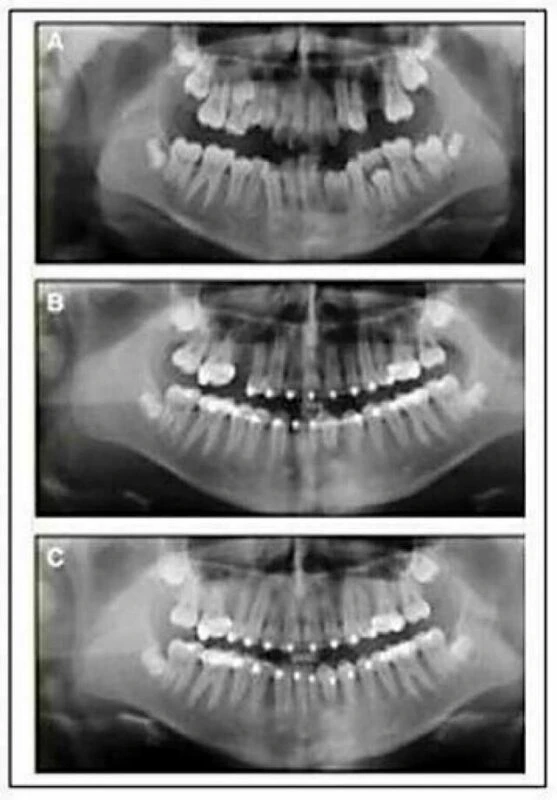

Khi dây cung Niti trở nên thụ động trong tất cả các khe mắc cài ở cả hai dây cung, thì bạn sẽ phải xác định lại xem mắc cài đó được gắn đúng chỗ hay không. Nếu mắc cài đã được gắn đúng, thì không còn răng nào bị xoay nữa. Nếu mắc cài nào bị gắn sai chỗ thì cần phải gắn lại để chỉnh lại xoay sai hoặc góc sai. Góc mắc cài bị sai được định giá bằng phim Panorama tiến trình, hoặc mẫu nghiên cứu tiến trình. Sai sót về chiều cao một răng nào đó có thể không cần phải gắn lại, vì những sai sót này sẽ được sửa dễ dàng trong giai đoạn hoàn tất.

Học viên phải lấy mẫu nghiên cứu triến trình vào cuối giai đoạn làm thẳng để kiểm tra về vị trí đặt mắc cài để người hướng dẫn kiểm tra. Dấu lấy bằng alginate bất kì tại phòng mạch và đổ mẫu mài chỉnh tại xưởng. Cần lấy dấu sáp cắn để mài mẫu theo tương quan, để tái lập cắn trung tâm bằng việc đặt mẫu lên bàn phẳng. Đối với những học viên điều trị những ca đầu tiên thì có thể cần phải gắn lại một số mắc cài.